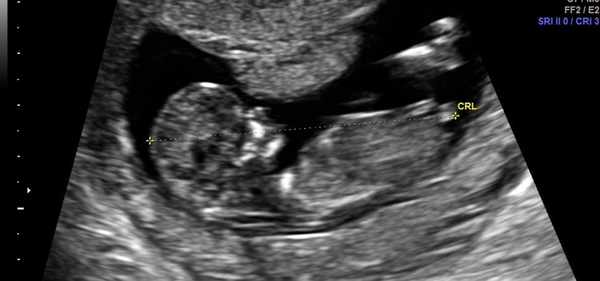

Hi ladies just hoping for some insight 🙏 wondering what u think I don't really understand the nub theory nor do I mind what gender my baby will be just intrigued to find out what other think 12wks 6days